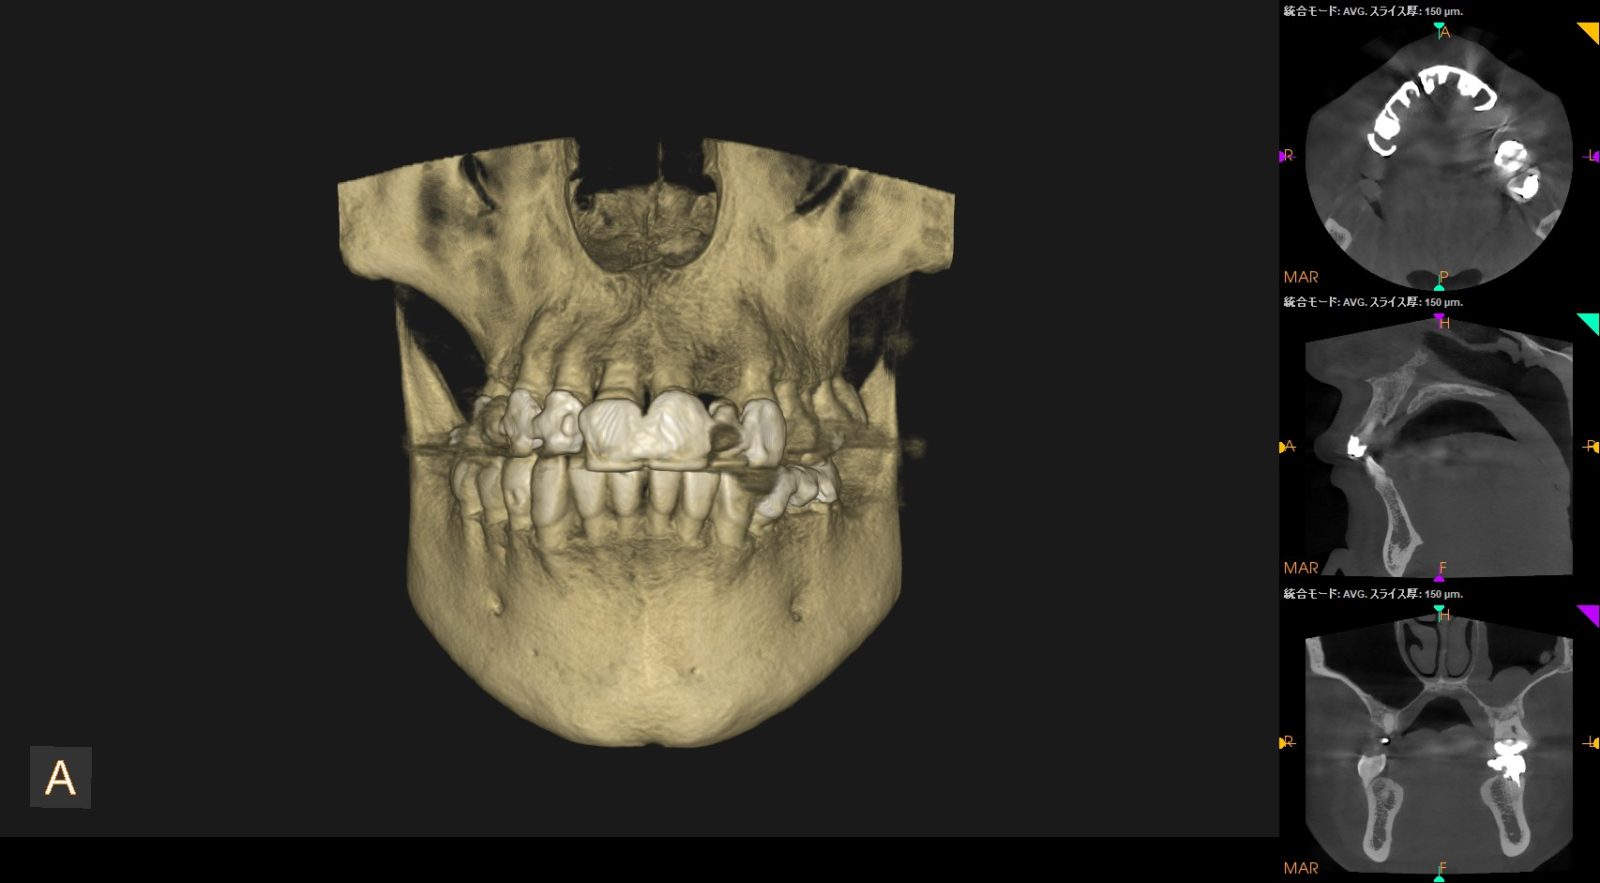

口の周辺は神経や血管などが多く存在し、少しでも傷つけてしまうと痺れや麻痺などの症状が残る恐れがあります。神経や血管を傷つけるのは正確な位置を把握せず、手探りの状態で処置を行ってしまうのが原因です。そういったリスクを減らすために、当院ではCTを活用しています。

CTとは顎の骨や神経、血管などを立体的に確認できる機器のことです。さまざまな角度から、神経や血管などの正確な位置を把握できるため、抜歯の正確性も高くなります。その結果、最小限の処置で済み、痛みや腫れを抑えた治療を実現しています。